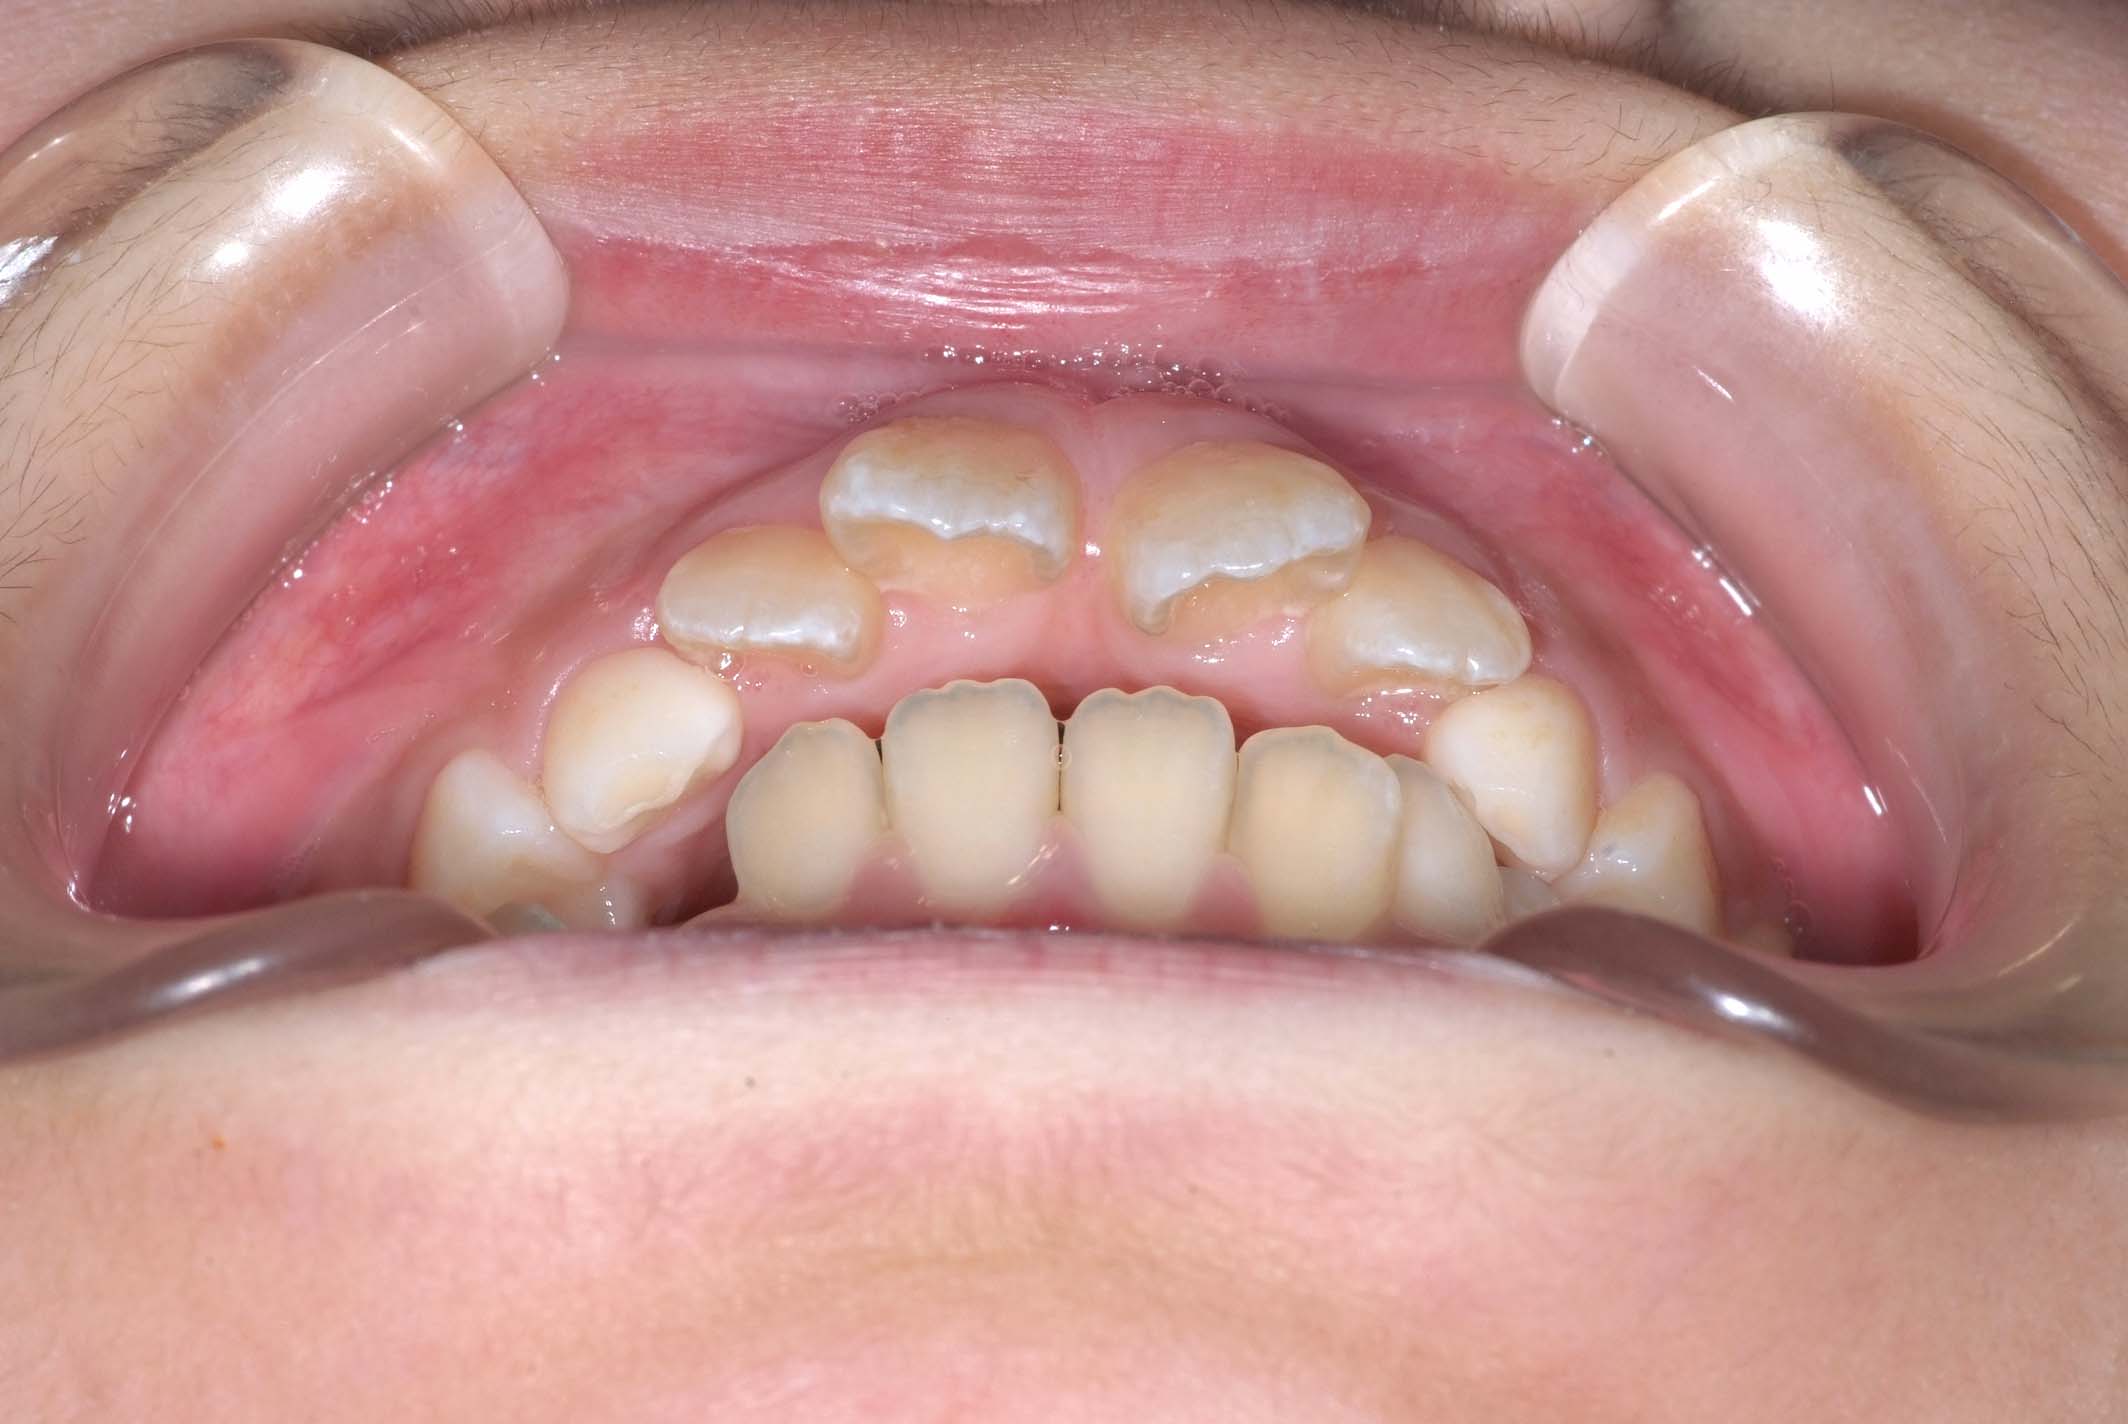

初診時年齢8才の女子で、前歯部開咬を気にして来院されました。

検査の結果、前歯部開咬と正中離開と上下顎前歯唇側傾斜を伴うアングルⅡ級1類不正咬合と診断しました。

前期治療は、リンガルアーチで正中離開を改善し、その後は歯列矯正用咬合誘導装置(マイオブレース)を使用して舌のトレーニングを行いました。後期治療は、上下左右4番を抜歯の上、セルフライゲーションブラケット装置(クリアティ・ウルトラ)で行いました。治療期間は前後期合わせて6年6ヶ月でした。通院回数:60回。